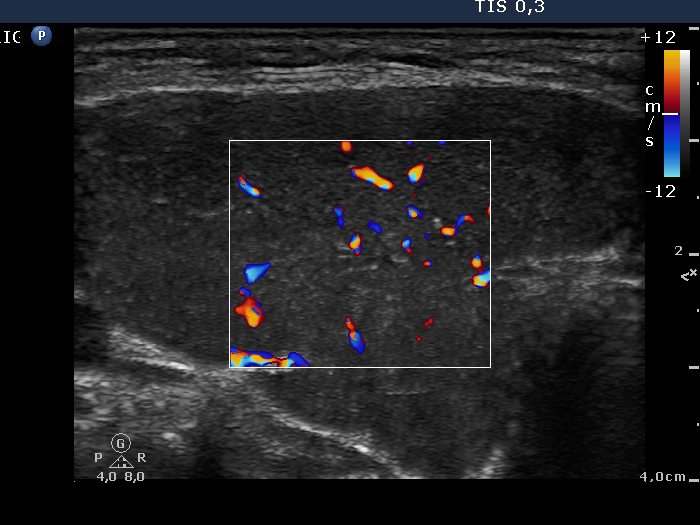

Ultrasonography: A hypoechogenic, inhomogeneous thyroid was found with increased vascularization.